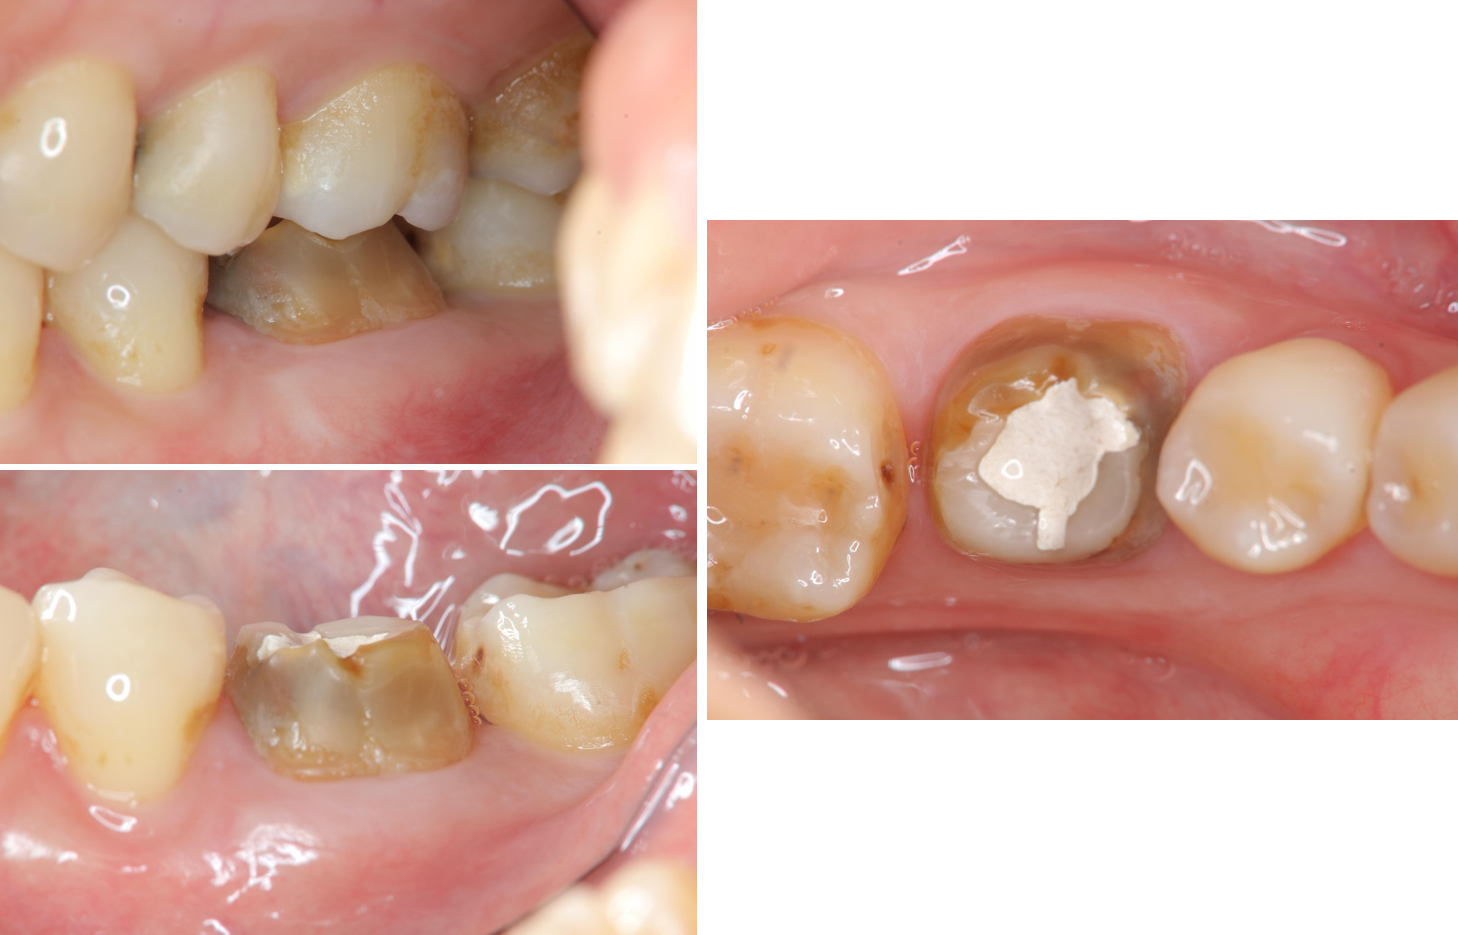

治療前,假牙脫落

治療前,根管治療後